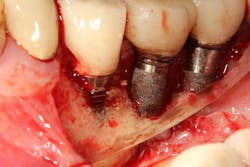

In a recent article discussing two case reports, Nd:YAG and 9.3 micron CO2 lasers were used to detoxify the inner lining of soft tissue surrounding ailing dental implants prior to tissue grafting (figures 1 and 2).12 Lasers can ablate the soft tissue of this particulate (metal) material while killing some of the residual translocated/invasive bacteria, thereby facilitating soft- and hard-tissue healing.

This video demonstrates laser detoxification of the inner lining of the soft-tissue flap, approximating failed dental implant and showing titanium particles embedded into the soft tissue with sparks flying during ablation:

In the two case reports, a laser detoxification approach that included both the implant fixture and the inner lining of the soft-tissue flap were combined with a previously published regenerative surgical algorithm.13 To achieve predictable tissue repair around diseased implants, proper decontamination of both the dental implant and the inner soft-tissue flap is necessary.